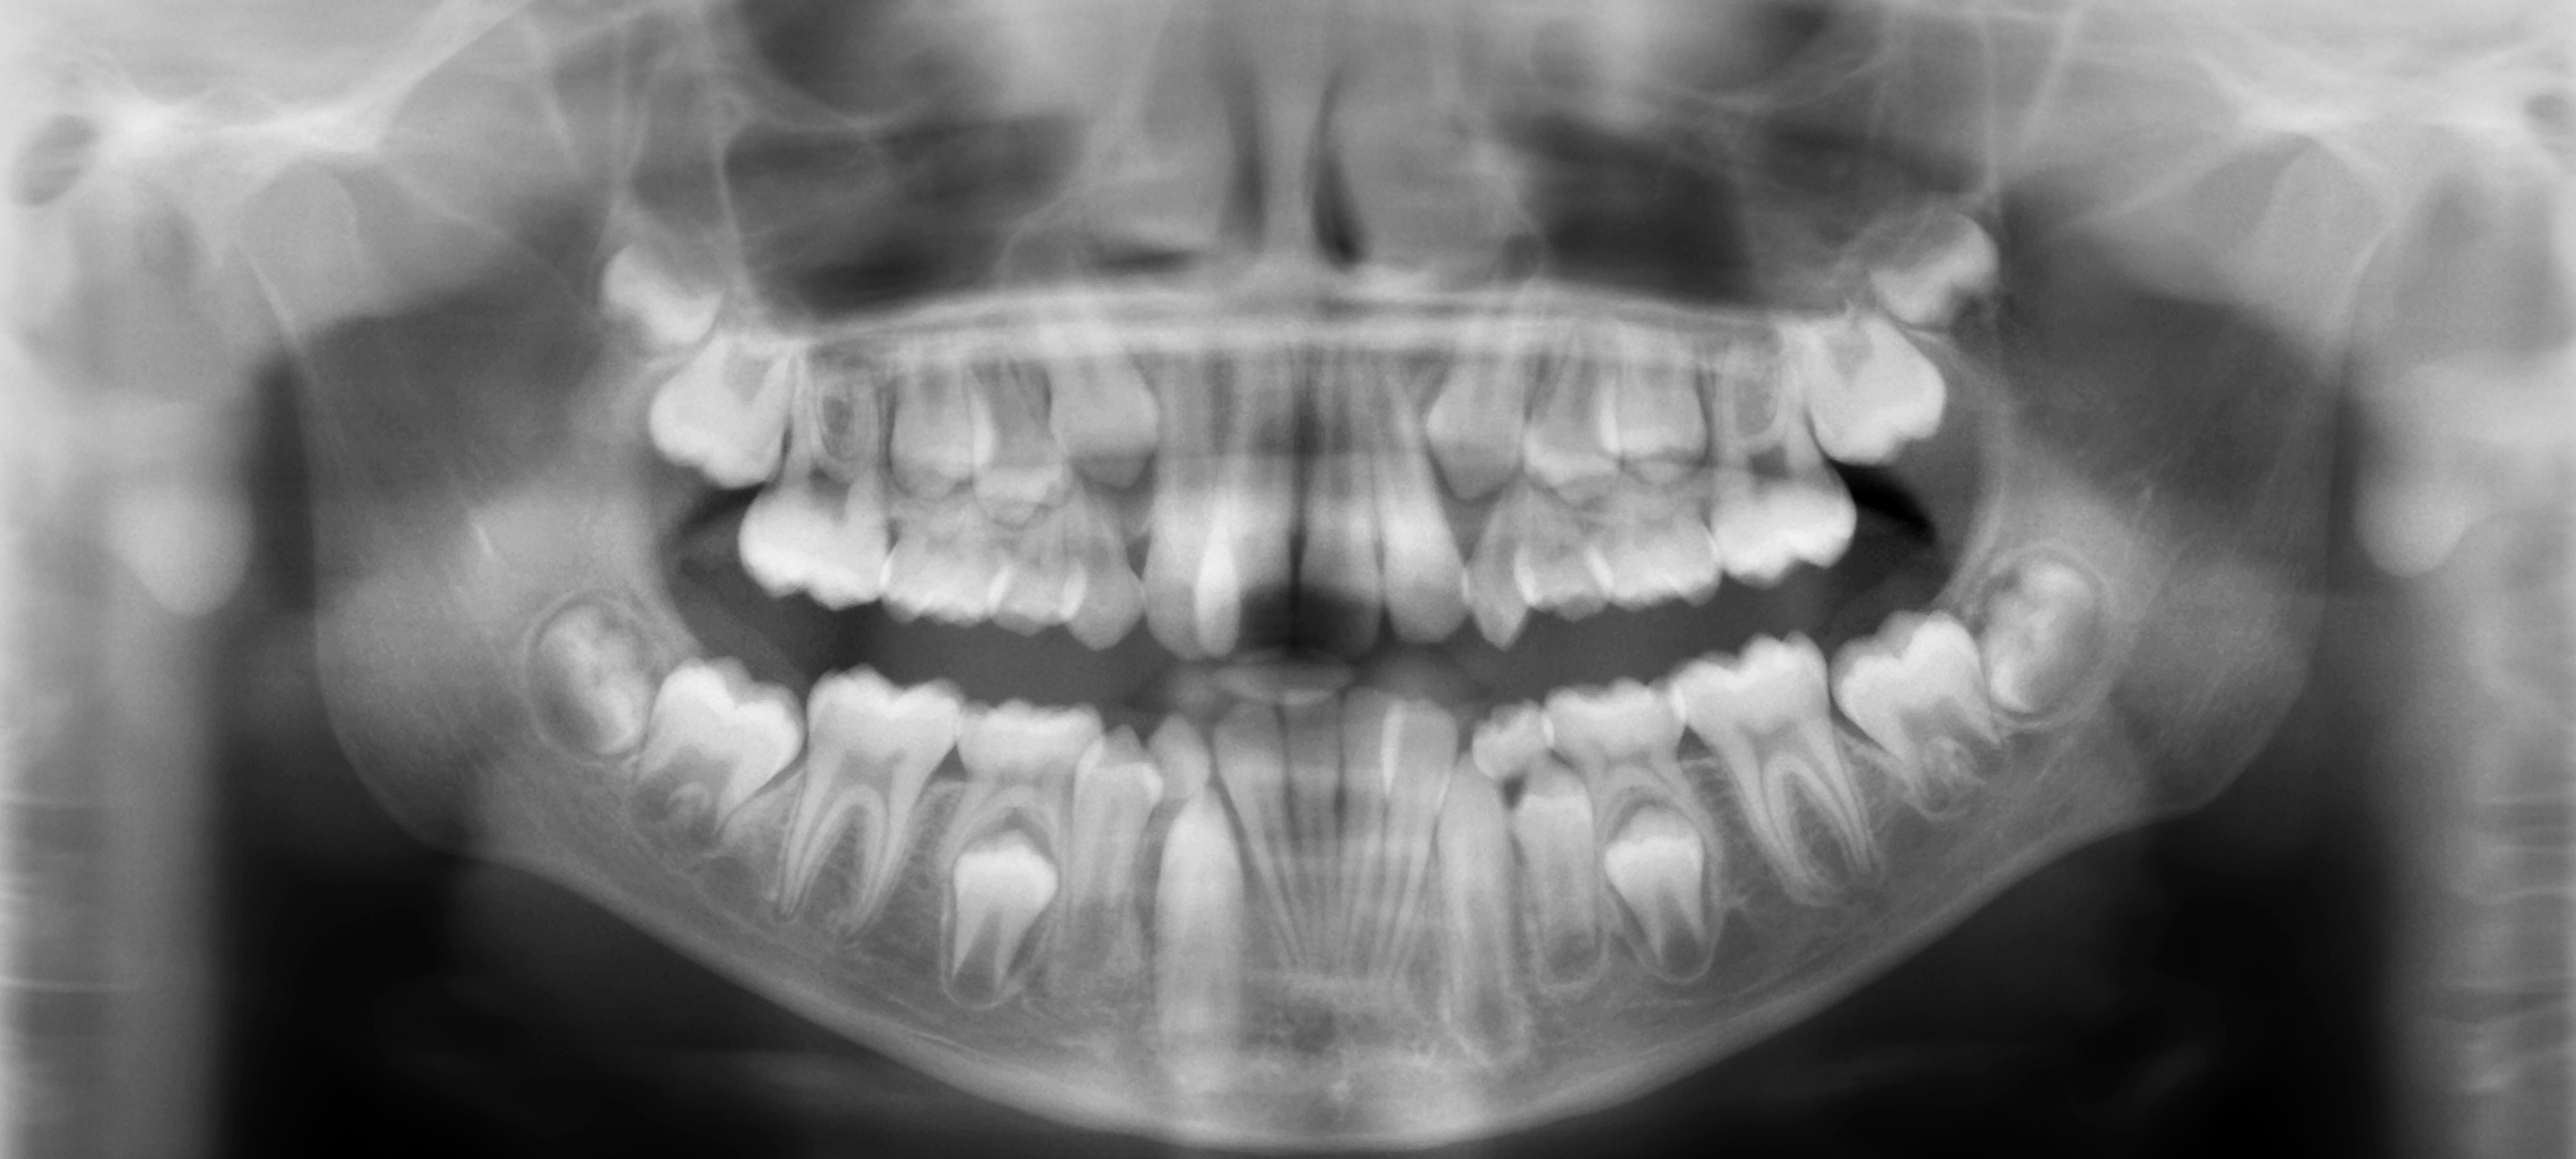

Panoramic images provide a useful overview of the teeth and jaws. They are commonly used for orthodontic surveys, to assess impacted teeth, and in implant planning

Panoramic images for the developing dentition show the presence and location of teeth